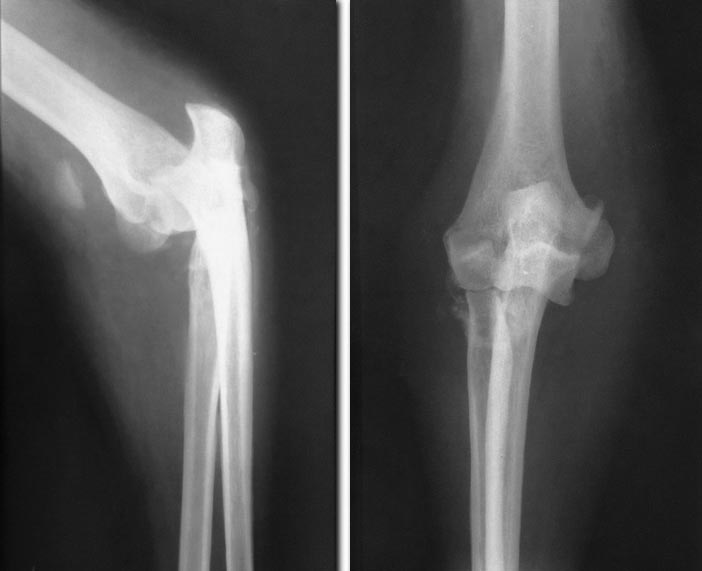

Застарелый переломовывих предплечья

Доброго времени суток. В клинику обратился мужчина, 46 лет, с переломовывихом предплечья. Со слов пациента, травма в результате падения с высоты собственного роста от 10.12.12г!!!

За мед. помощью обратился в травм. пункт по месту жительства, где повреждение было расценено как ушиб локтевого сустава, вследствие чего не выполнялись р-граммы, устранение вывиха и адекватная иммобилизация. В связи с усилением болевого синдрома и уменьшением амплитуды движений в локтевом суставе, 18.01.13г. обратился в нашу клинику.Глубокоуважаемые коллеги, необходим ваш совет в выборе тактики лечения.